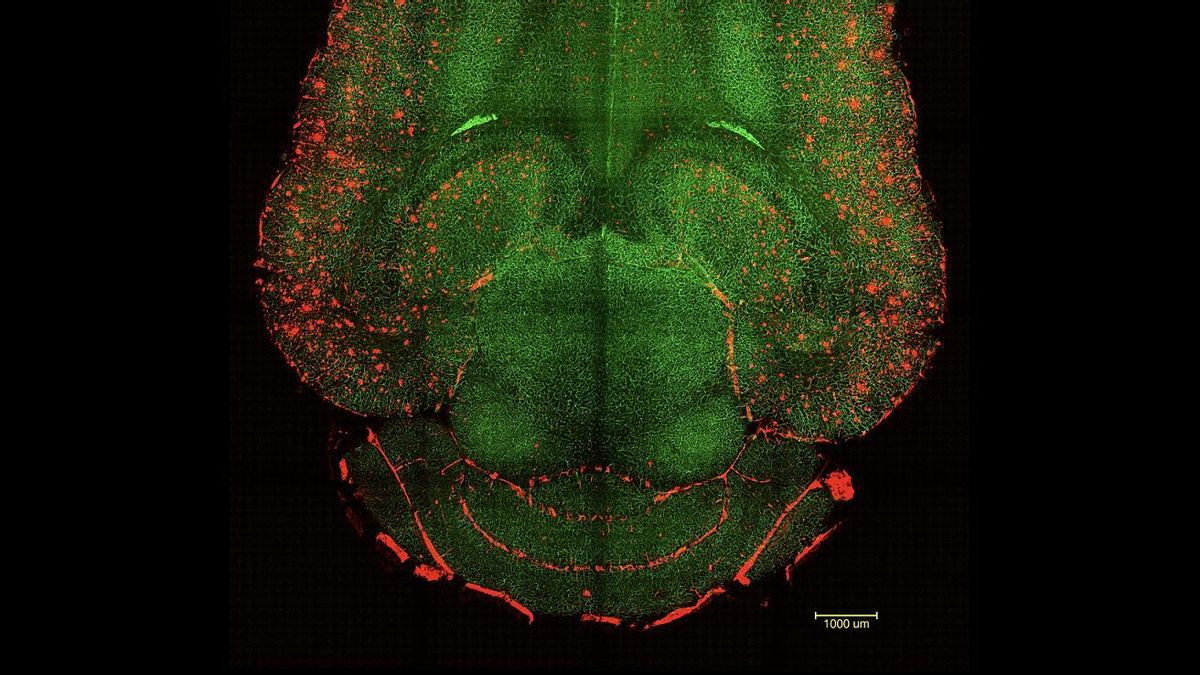

Los investigadores han diseñado una novedosa técnica centrada en restaurar la salud vascular del cerebro y lograr así que este mismo sea el que repare las funciones perdidas por la enfermedad...